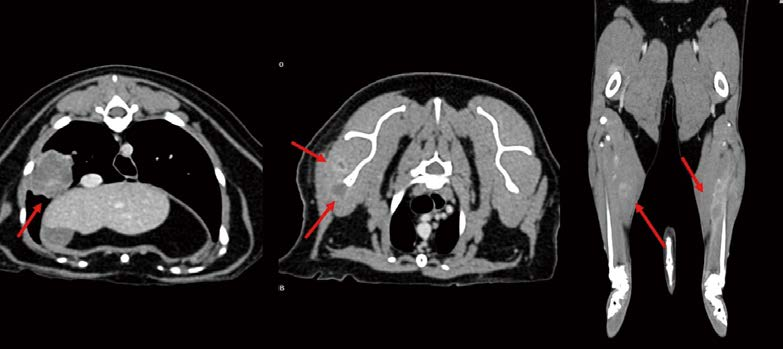

[대한수의사회지 24.png

개와 비교 시, 고양이 원발 폐종양의 digits로의 전이가 좀 더 잘 관찰되어서 Lung digit syndrome 이라는 용어를 일반적으로 쓰고 있지만, 고양이에서 폐종양은 digit 뿐만 아니라, 전신 여러 군데로 전이가 잘 된다고 알려져 있습니다. MODAL syndrome(Muscle/ocular/digit/aorta/lung) 용어가 좀 더 임상적으로 활용되면 좋을 것 같습니다. 다음 고양이는 pulmonary adenocarcinoma가 전지, 후지 근육으로 전이된 MODAL syndrome 환자입니다.